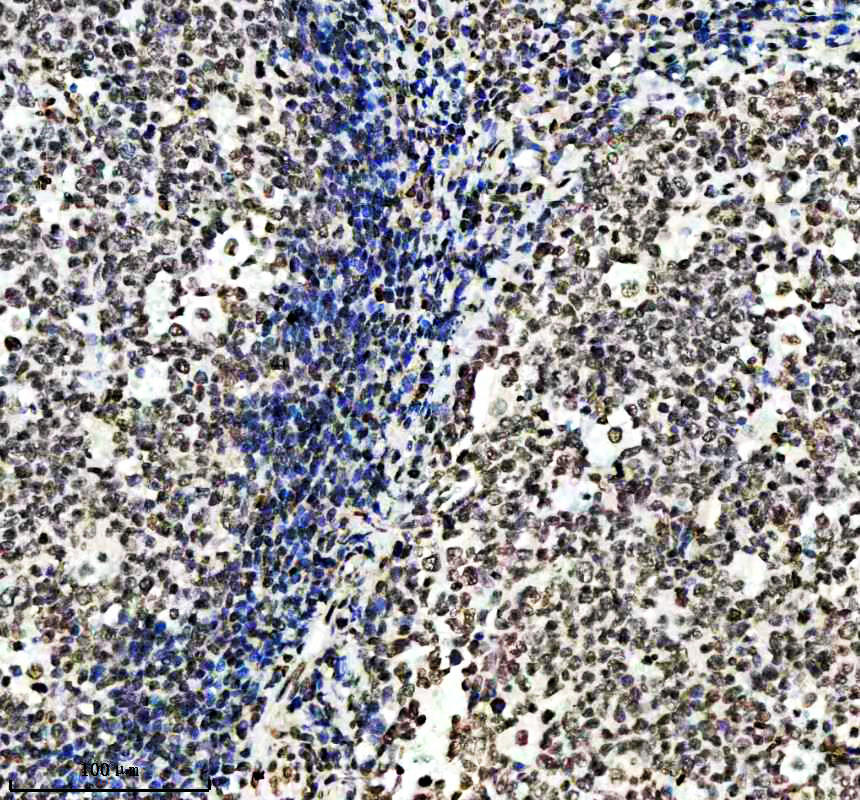

IHC analysis of Histone H3 (acetyl K14) using anti-Histone H3 (acetyl K14) antibody (BM4151) .

Histone H3 (acetyl K14) was detected in a paraffin-embedded section of human lymphoma tissue. The tissue section was incubated with rabbit anti-Histone H3 (acetyl K14) Antibody (BM4151) at a dilution of 1:200 and developed using HRP Conjugated Rabbit IgG Super Vision Assay Kit (Catalog # SV0002) with DAB (Catalog # AR1027) as the chromogen.

IHC analysis of Histone H3 (acetyl K14) using anti-Histone H3 (acetyl K14) antibody (BM4151) .

Histone H3 (acetyl K14) was detected in a paraffin-embedded section of human lymphoma tissue. The tissue section was incubated with rabbit anti-Histone H3 (acetyl K14) Antibody (BM4151) at a dilution of 1:200 and developed using HRP Conjugated Rabbit IgG Super Vision Assay Kit (Catalog # SV0002) with DAB (Catalog # AR1027) as the chromogen.